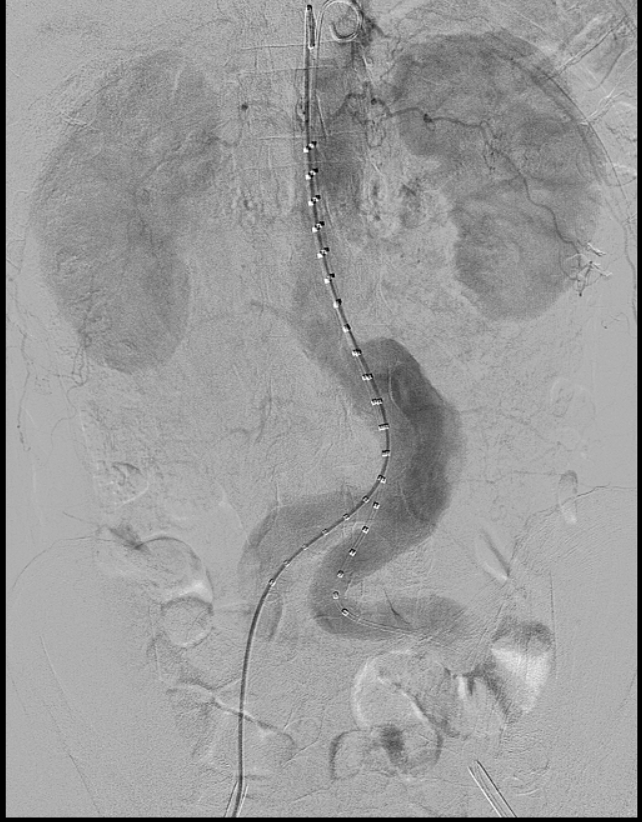

近日,文山州人民医院胸外科心脏大血管外科首次引进G-iliac髂动脉分叉支架系统,为一位68岁的腹主动脉瘤、双髂总动脉瘤患者,成功施行州内首例“腹主动脉瘤、左髂总动脉瘤覆膜支架腔内隔绝、右侧髂总动脉瘤覆膜支架腔内隔绝+右侧髂内动脉分叉支架重建术(IBD支架置入术)”。目前患者术后恢复良好,已康复出院。

腹主动脉瘤可同时累及单侧或双侧髂总动脉,髂内动脉受累及是孤立性髂动脉瘤和腹主动脉瘤合并髂总动脉瘤病变中的常见现象,采用腹主动脉瘤腔内修复术治疗时,需要考虑保留或牺牲髂内动脉的问题,在施行累及髂动脉瘤的支架手术时,经常需要栓塞或闭塞髂内动脉,封堵髂内动脉后可能带来相应的并发症,如:臀肌缺血萎缩、跛行、性功能障碍、结肠缺血、脊髓缺血、臀肌或直肠坏死等。采用G-iliac髂动脉分叉支架系统,适用于腹主动脉瘤合并髂动脉瘤或孤立性髂总动脉瘤的患者,保障患者的髂内动脉血流通常,减少并发症的发生。